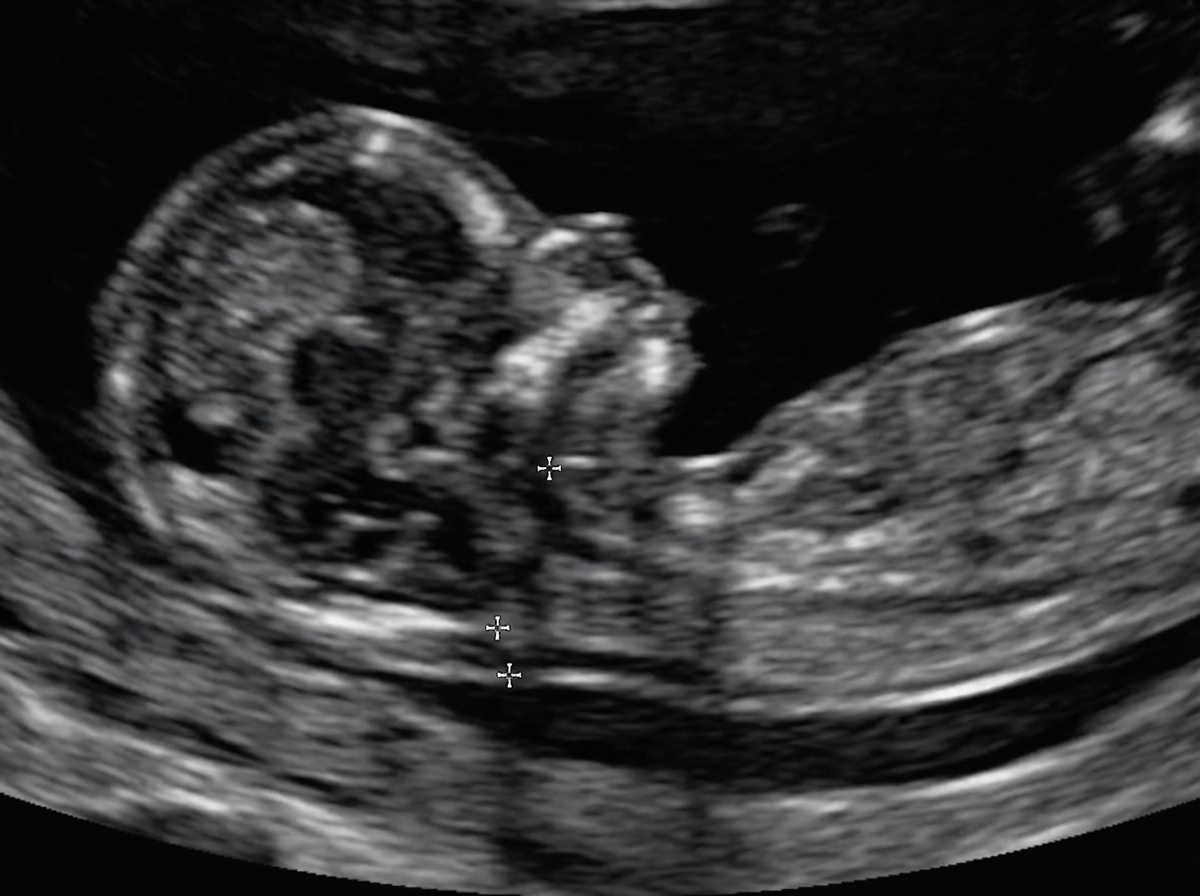

An ultrasound measures a parameter at 3.7 mm. What does this measurement indicate?

Explanation: ***A finding higher than normal*** - A **nuchal translucency (NT)** measurement of 3.7 mm exceeds the normal threshold of **<3.0-3.5 mm** at 11-13+6 weeks gestation. - This increased NT is associated with **higher risk of chromosomal abnormalities** like **Down syndrome (Trisomy 21)** and **congenital heart defects**. *A normal finding* - Normal **nuchal translucency** should be **less than 3.0-3.5 mm** depending on gestational age and laboratory standards. - A measurement of 3.7 mm clearly exceeds the established **upper limit of normal** for NT screening. *A finding lesser than normal* - **Nuchal translucency** measurements are concerning when they are **increased**, not decreased. - Lower NT values are generally **reassuring** and associated with lower risk of chromosomal abnormalities. *The scan should be repeated at 18 weeks* - **Nuchal translucency** is specifically measured between **11-13+6 weeks** gestation when it is most accurate. - At 18 weeks, NT measurement is **no longer valid** as the nuchal fold naturally resolves by this time.